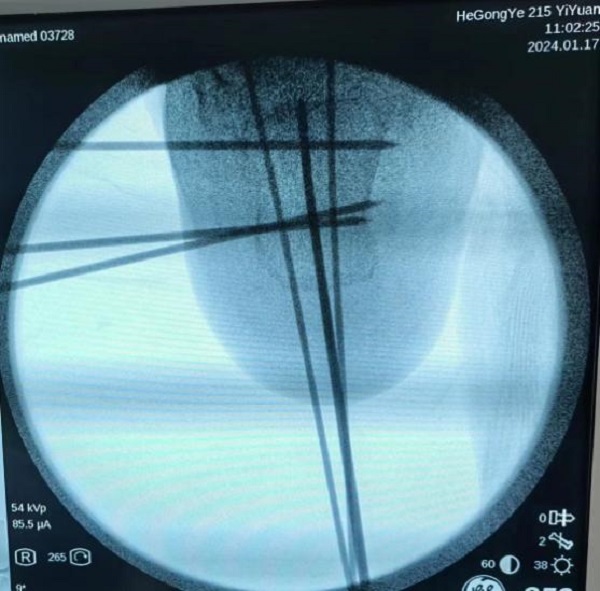

病情研判过程中,考虑到孩子年龄尚小,必须以最小的创伤完成治疗,用最快的速度让孩子恢复。宋强主任多频次组织团队阅片讨论,探究最佳诊疗方案。讨论认为,此例跟骨骨折涉及关节面,并且出现关节面塌陷,手术指征非常明确。在与家属充分沟通取得信任和支持后,宋强主任团队决定为小铎施行踝关节镜下微创手术治疗。考虑到儿童的病情进展较快,伤后第3天,手术便紧急开展。

手术过程中,关节镜从微小的窗口进入患儿体内探查,将病灶部位情形以最大视角、最佳角度呈现在监视画面中。关节镜直视下发现,关节面分离移位的程度远超影像资料提供的片面数据,手术的难度与复杂程度比预想的要大很多。在关节镜的辅助下,宋强主任团队专注谨慎,每一个步骤、每一次下刀都力争分毫无差,凭借多年累积的专业经验和技术水平,在约一个半小时的精细操作后,关节成功复位,手术精准且顺利的完成。

复位后,达到满意效果

关节面成功复位,创伤也很小